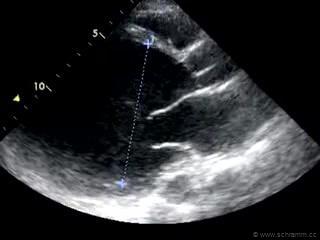

Wenn das Herz nicht in der Lage ist das benötigte Herzzeitvolumen (CO) (In Ruhe etwa 5 l/min beim Erwachsenen) zur Verfügung zu stellen und der Blutdruck (MAP) daraufhin abfällt reagiert der Organismus mit einer peripheren Vasokonstriktion (SVR ↑) welche man in diesem Fall als Kreislauf-Zentralisierung bezeichnet, d.h. es kommt zu einer Umverteilung des zirkulierenden Blutes aus der Körperperipherie auf die überlebenswichtige Organe. Das Blut staut über die Lungenstrombahn zurück, woraus eine Erhöhung des zentralen Venendrucks (CVP) resultiert, was u.U. zu sichtbar gestauten Halsvenen führt. Die periphere Vasokonstriktion hilft dabei den MAP ansteigen zu lassen, denn MAP=CVP+CO·SVR. Der höhere alveolo-kapilläre Druckgradient kann die Ursache für ein Lungenödem sein. Die kausale Therapie besteht in einer frühestmöglichen Koronarreperfusion (perkutane Koronarintervention) bzw. systemischen Fibrinolyse bzw. operativen Koronarrevaskularisation (Notfallbypass).